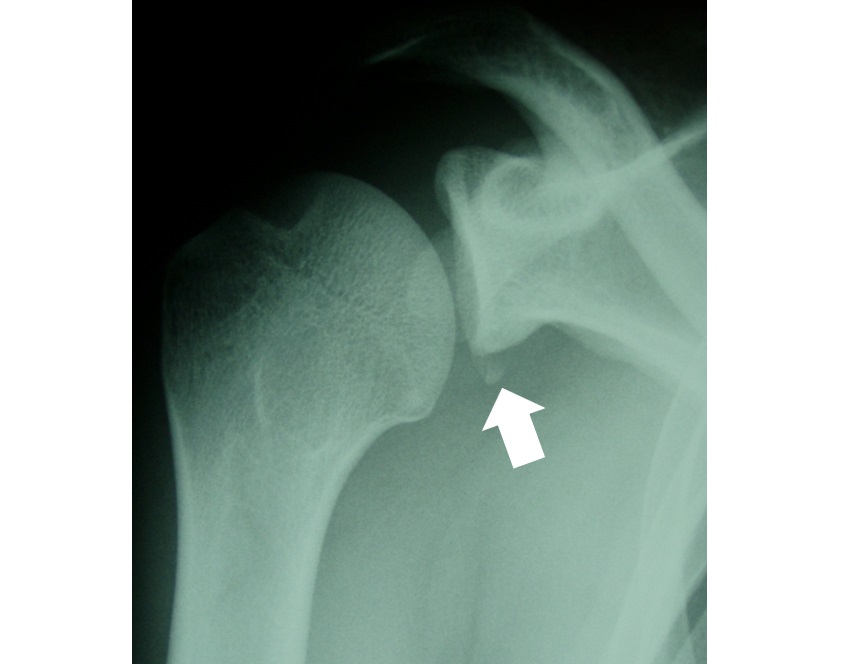

另外,確認對關節穩定性很重要的肩胛骨關節盂下緣前方(Bankart照片4)和肱骨頭後外側(Hill-Sachs)的損傷也是有必要的。

照片4 關節邊緣的撕脫骨折。或者說是肩胛骨關節盂下緣前方骨折